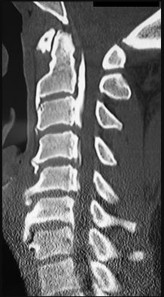

A 25-yo man sustains the injury shown in Figures 29a and 29b as a result of high-speed trauma. Examination reveals diffuse weakness in the lower extremities that is slightly worse on the right side, and decreased rectal tone and sensation. A CT scan is shown in figures 29c and 29d. Definitive treatment of the injury to the spine is delayed because of a severe pulmonary contusion. At 15 days after the injury, the patient’s neurological status remains unchanged. Management should now consist of